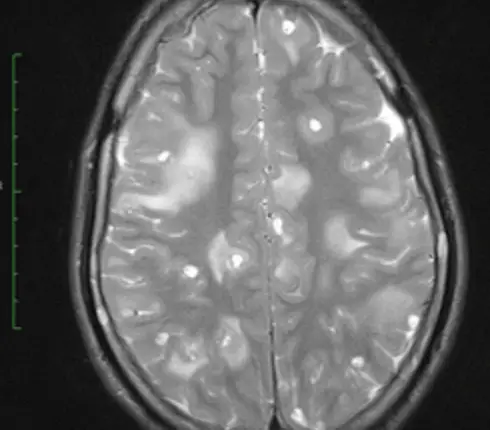

Published by medical professionals Mohd Ilyas and Vikrant Mahajan, the pair shared CT scans of the young girl’s legs and brain.

The CT scans show that, as a result of eating the undercooked meat, the girl’s brain and legs were full of parasites, leading E.R. Doctor Sam Ghali M.D. to post them to X (formerly known as Twitter), calling them ‘one of the craziest CT scans [he’s] ever seen’.

This then caused her seizures due to ‘innumerable’ small lesions all over her brain and the muscles throughout her body.